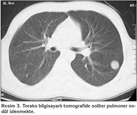

Yirmi ya??nda erkek hastan?n, alt? ayd?r halsizlik ve ?? ayd?r sol yan a?r?s? yak?nmalar? vard?. Askerlik g?revini yapmakta iken Verem Sava? Dispanseri taraf?ndan yap?lan taramada ?ekilen PA akci?er grafisinde ku?kulu lezyon saptanmas? ?zerine hastanemize sevk edildi. Fizik muayene bulgular? normal saptand?; hastan?n ate?i; 36?C, nabz?; 63 vuru/dakika, TA; 100/65 mmHg, solunum say?s?; 16/dakika idi. ?z ge?mi?inde ve yak?n aile anamnezinde bir ?zellik yoktu. Bir paket/y?l sigara ?yk?s? vard?. Tam kan, tam idrar, sedimentasyon ve rutin biyokimya incelemeleri normal s?n?rlarda tespit edildi. PA ve lateral akci?er grafilerinde sol hemitoraksta ?st zonda SPN ile uyumlu g?r?n?m mevcuttu (Resim 1,2). Toraks bilgisayarl? tomografi (BT)'de; sol akci?er ?st lob apikoposterior segmentte, periferik yerle?imli, yakla??k 2 x 2 cm ?ap?nda, d?zg?n kont?rl?, sferik SPN ile uyumlu g?r?n?m saptand?. Mediastende patolojik boyutlarda lenfadenopati yoktu ve tan?mlanan g?r?n?m haricinde infiltrasyon ve kitle saptanmad? (Resim 3). Hasta balgam ??karamad??? i?in al?nan mide suyu asido-alkalo rezistan basil (ARB) negatif olarak de?erlendirildi ve k?lt?r?nde ?reme olmad?. Bronkoskopide endobron?iyal lezyon g?zlenmedi. Bron? lavaj? ARB negatifti ve k?lt?r?nde ?reme olmad?. Bron? lavaj? sitolojik incelemesi malignite y?n?nden negatif olarak raporland?. Kist hidatik i?in yap?lan ELISA testi negatif bulundu. Bat?n ultrasonografi (USG) incelemesi normaldi. Olgudan SPN etyolojisini ayd?nlatabilmek i?in g???s cerrahisi kons?ltasyonu al?nd? ve olguya kist hidatik ?n tan?s?yla operasyon planland?. Torakotomi ile sol ?st lobda saptanan 2 x 2 cm'lik nod?le wedge rezeksiyon uyguland? ve perioperatif patoloji kons?ltasyonu istendi. Elde edilen materyalin makroskobik incelenmesinde malignite saptanmamas? ?zerine operasyon sonland?r?ld?. Eksizyonel biyopsi ?rne?inin mikroskobik incelemesi intralober pulmoner sekestrasyon (Kesitlerde akci?er parankimi bulgular? g?steren iyi s?n?rl? nod?ler lezyon izlenmektedir. G?m??leme y?ntemiyle yap?lan incelemede lezyonda yayg?n olarak retik?lin liflerinde art??, baz?lar? hiperplastik g?r?n?mde damar yap?lar? ve d?zensiz bron? alveol ?at?lar? g?r?lmektedir) olarak raporlanm??t?r.

Radyolojik olarak PS'lerin, kom?ulu?unda lokal amfizemat?z de?i?iklikleri i?eren, genellikle kistik ?zelliklere sahip olan veya olmaks?z?n ayr? bir kitle lezyonu ?eklinde g?r?ld??? bilinmektedir (1,7). Sunulan olgunun en ?nemli ?zelliklerinden biri d?zg?n s?n?rl? ve yuvarlak g?r?n?ml? SPN olmas?yd?. PS'ler i?in neredeyse tipik olan alt lob yerle?imi d???nda sol ?st lob apikoposterior yerle?imi olmas? da g?z ?n?ne al?nd???nda, bu iki ?zelli?i ta??yan PS olgusuna literat?rde rastlanmam??t?r. Olgu PS i?in tipik ?zellikleri ta??mad??? i?in ?n tan?da daha ?ok t?berk?loma, kist hidatik gibi SPN ay?r?c? tan?s?nda rol alabilecek di?er nedenler d???n?lm??t?r (12). Bu sebeple, PS tan?s? i?in gerekli olan, anormal olu?umu besleyen sistemik arterin g?sterilmesine y?nelik aortografi, BT anjiyografi ve manyetik rezonans anjiyografi tetkikleri yap?lmam??t?r. PS ?n tan?s? olsayd?, besleyici sistemik arterin g?sterilmesine y?nelik? ?ok ?nemli bir yeri olan spiral BT anjiyografinin yap?lmas? gerekirdi. Yap?lan d?rt olguluk bir seride spiral BT anjiyografi ile PS tan?s? kondu?u bildirilmi?tir (3). Bu olgunun ise postoperatif patolojik incelemesi sonucu PS oldu?u anla??lm??t?r.